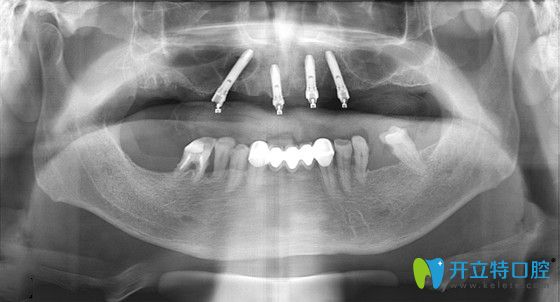

鉑爾口腔的種植醫(yī)生吳爽杰院長,從張大爺?shù)呐钠瑱z查中了解到,雖然張大爺?shù)难例X缺失多年,但牙槽骨條件還算可以,比較適合做種植牙修復。因為,張大爺?shù)娜谘例X幾乎全部都缺失了,為了減少種植手術的痛苦、降低費用,吳院長建議張大爺做ALL-ON-4即刻負重的種植技術。

張大爺即刻負重手術過程全記錄:首先,吳院長運用了三維數(shù)字軟件,精準的測量了張大爺?shù)难啦酃敲芏?、高度、寬度等信息,確定了種植位置,經(jīng)過1個多小時,復雜而有序的專業(yè)操作后,完成了種植體的種植操作;然后又為張大爺安裝了基臺、牙冠;當天回到家就能吃東西啦!

ALL-ON-4即刻負重技術,只用4--6顆種植體就能恢復半口牙的咀嚼功能▼

東營鉑爾口腔all-on-4種植牙優(yōu)勢:只需要種植4--6顆種植體就能恢復半口牙;而且在拔牙的同時,就能一次性植入種植體,減少種植時間、種植費用;術后出血少、腫脹輕微、當天就能吃東西。